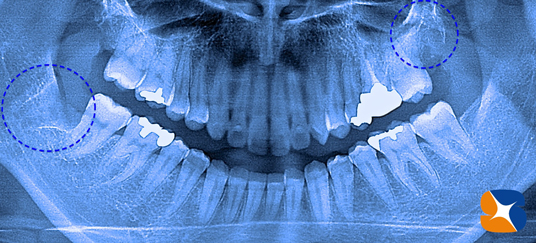

レントゲン撮影の結果、右下の親知らず左上の親知らず歯茎の中に完全に隠れている厄介な歯である事が判明しました。患者様のリクエストに出来る限り応えられるように努力しました。

横向きの親知らず 静脈麻酔鎮静 保険 大阪 奈良 歯茎の中に完全に隠れている親知らずの歯の抜歯は、やはり難しいです。 静脈麻酔鎮静法を使っての抜歯を行いました。

横向きの親知らず 静脈麻酔鎮静 保険 大阪 奈良 歯茎を開くと、下顎の骨の中に完全に包囲されている親知らずの歯を確認することが出来ました。